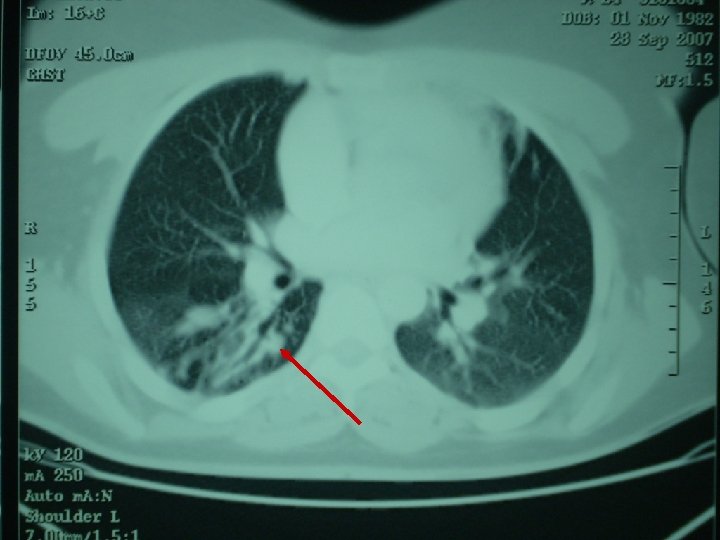

Paciente natural de Marruecos con adenopatías cervicales Evolución: BAAR de esputo: NEGATIVOS TAC de tórax: lesiones nodulares en lóbulos superiores y pequeño infiltrado intersticio-alveolar en segmento 6 de LID. TAC cervical: Adenopatías cervicales derechas que captan contraste, con centro hipoatenuado en su interior en relación con necrosis, y cuyo tamaño oscila entre 1, 5 y 2, 5 cms.

Paciente natural de Marruecos con adenopatías cervicales Evolución: Fibrobroncoscopia: Ausencia de orificio de entrada del B 6 derecho, que muestra una coloración blanquecina y muy friable. Se realiza BAS. Resultado BAS: No se observan BAAR, se envía para cultivo.

Paciente natural de Marruecos con adenopatías cervicales Evolución: PAAF de adenopatía: abundantes BAAR. Cultivo de Lowenstein (de PAAF cervical y BAS): Mycobacterium tuberculosis complex. Antibiograma: sensible Pirazinamida, Estreptomicina. a Rifampicina, Isoniacida,